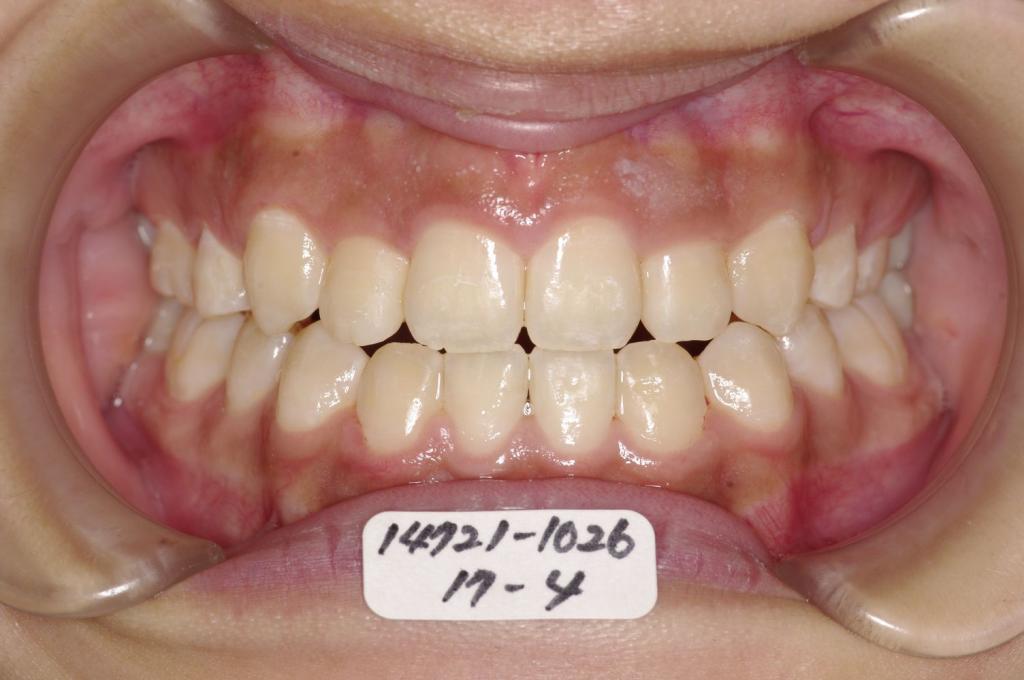

歯欠損の矯正治療

(治療期間、治療前後写真、治療方法、費用)WORKS

下記の実績データをクリックして頂くと「性別」、「治療開始年齢」、「治療終了年齢」、「治療方法(矯正治療装置写真含む)」、「治療終了までの費用」など、詳細な矯正治療データをご覧頂けます。